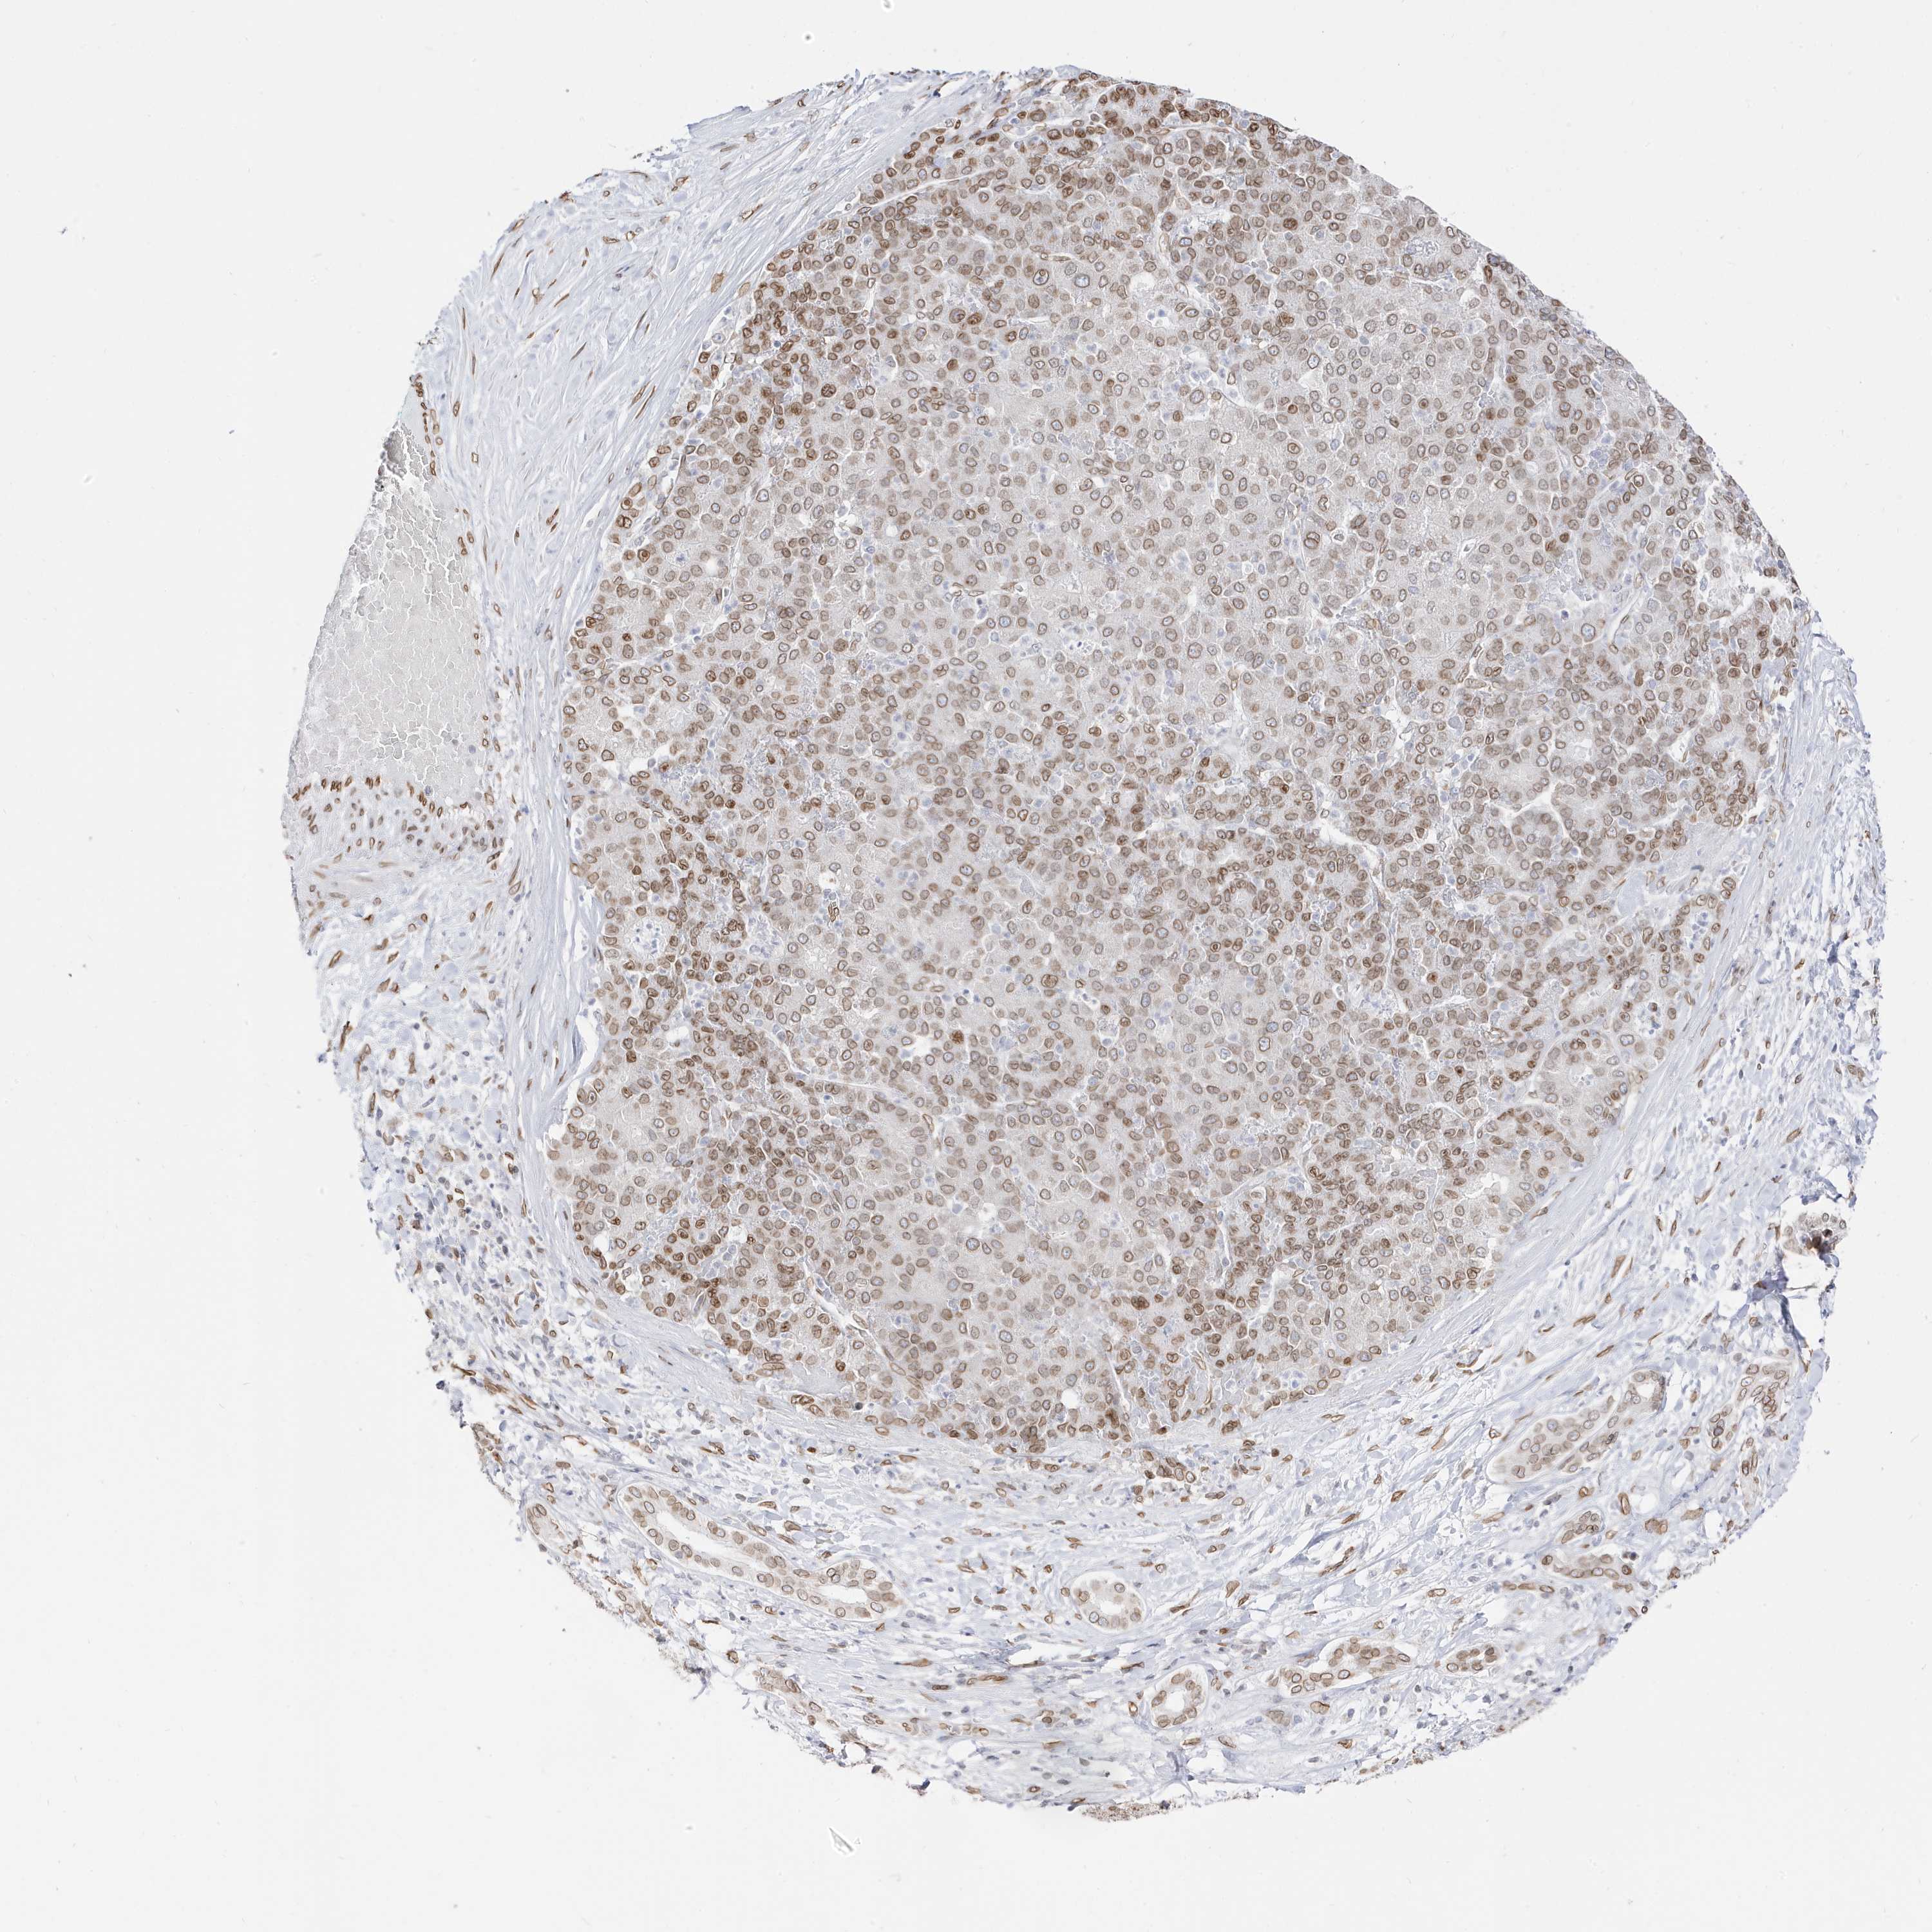

LIVER CANCER - Protein expressioni

A mouse-over function shows sample information and annotation data. Click on an image to view it in a full screen mode. Samples can be filtered based on level of antibody staining by selecting one or several of the following categories: high, medium, low and not detected. The assay and annotation is described here.

Note that samples used for immunohistochemistry by the Human Protein Atlas do not correspond to samples in the TCGA dataset.

Antibody stainingi

Antibody staining in the annotated cell types in the current human tissue is reported as not detected, low, medium, or high, based on conventional immunohistochemistry profiling in selected tissues. This score is based on the combination of the staining intensity and fraction of stained cells.

Each image is clickable and will lead to virtual microscopy that enables deeper exploration of all samples and also displays staining intensity scores, fraction scores and subcellular localization as well as patient and tissue information for each sample.

Antibody HPA029090

Staining

High

Medium

Low

Not detected

Intensity

Strong

Moderate

Weak

Negative

Quantity

>75%

75%-25%

<25%

None

Location

Nuclear

Cytoplasmic/membranous

Cytoplasmic/membranous,nuclear

Cholangiocarcinoma

Carcinoma, Hepatocellular, NOS